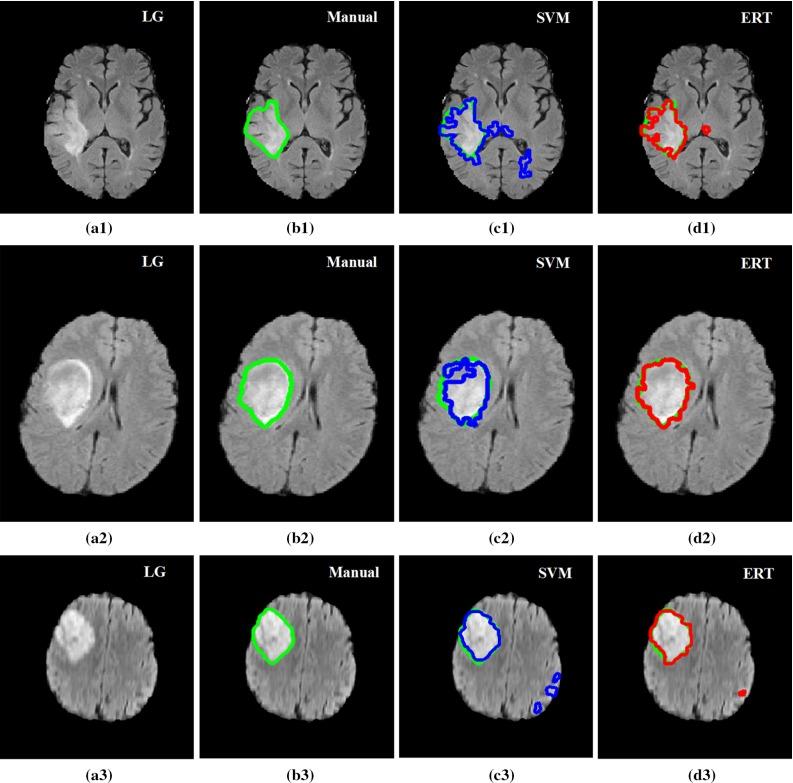

The method is based on superpixel technique and classification of each superpixel. A number of novel image features including intensity-based, Gabor textons, fractal analysis and curvatures are calculated from each superpixel within the entire brain area in FLAIR MRI to ensure a robust classification. Extremely randomized trees (ERT) classifier is compared with support vector machine (SVM) to classify each superpixel into tumour and non-tumour.

The proposed method is evaluated on two datasets: (1) Our own clinical dataset: 19 MRI FLAIR images of patients with gliomas of grade II to IV, and (2) BRATS 2012 dataset: 30 FLAIR images with 10 low-grade and 20 high-grade gliomas. The experimental results demonstrate the high detection and segmentation performance of the proposed method using ERT classifier. For our own cohort, the average detection sensitivity, balanced error rate and the Dice overlap measure for the segmented tumour against the ground truth are 89.48 %, 6 % and 0.91, respectively, while, for the BRATS dataset, the corresponding evaluation results are 88.09 %, 6 % and 0.88, respectively.

在两个数据集上对所提出的方法进行了评估:(1)我们自己的临床数据集:19例II至IV级胶质瘤患者的MRI FLAIR图像,以及(2)BRATS 2012数据集:30张FLAIR图像,其中有10例低级别胶质瘤和20例高级别胶质瘤。实验结果表明,使用ERT分类器的所提出方法具有较高的检测和分割性能。对于我们自己的队列,分割肿瘤相对于真实情况的平均检测灵敏度、平衡错误率和Dice重叠度量分别为89.48%、6%和0.91,而对于BRATS数据集,相应的评估结果分别为88.09%、6%和0.88。